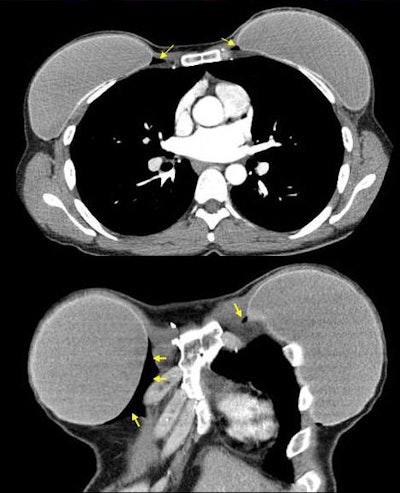

Axial and coronal CT images demonstrate gas collecting in the medial retropectoral space in this patient five years after bilateral mastectomies with silicone implant reconstruction. Image courtesy of Dr. John M. Lewin.

After receiving a negative breast ultrasound, the patient also underwent a chest CT exam at a local hospital to investigate mild shortness of breath. Findings were negative except for a small amount of gas that could be seen surrounding the breast implants within the implant capsule. The woman had flown the day before from New York to Denver, also known as the Mile High City for its altitude. From Denver, she drove over a mountain pass with an elevation of 10,600 ft to her home in a town with an elevation of 8,000 ft above sea level (Plast Reconstr Surg, March 2013, Vol.131:3, pp. 465e-467e).

Decompression had caused dissolved gas in the blood to come out of solution and fill a potential space between the implant and the capsule, Lewin explained. Because the compressibility of tissue is much greater than that of silicone gel or saline, the surrounding tissue expanded to a much greater degree than the implant. This created an empty space between the capsule and the implant, and dissolved gas from the blood came out of solution to fill the vacuum.